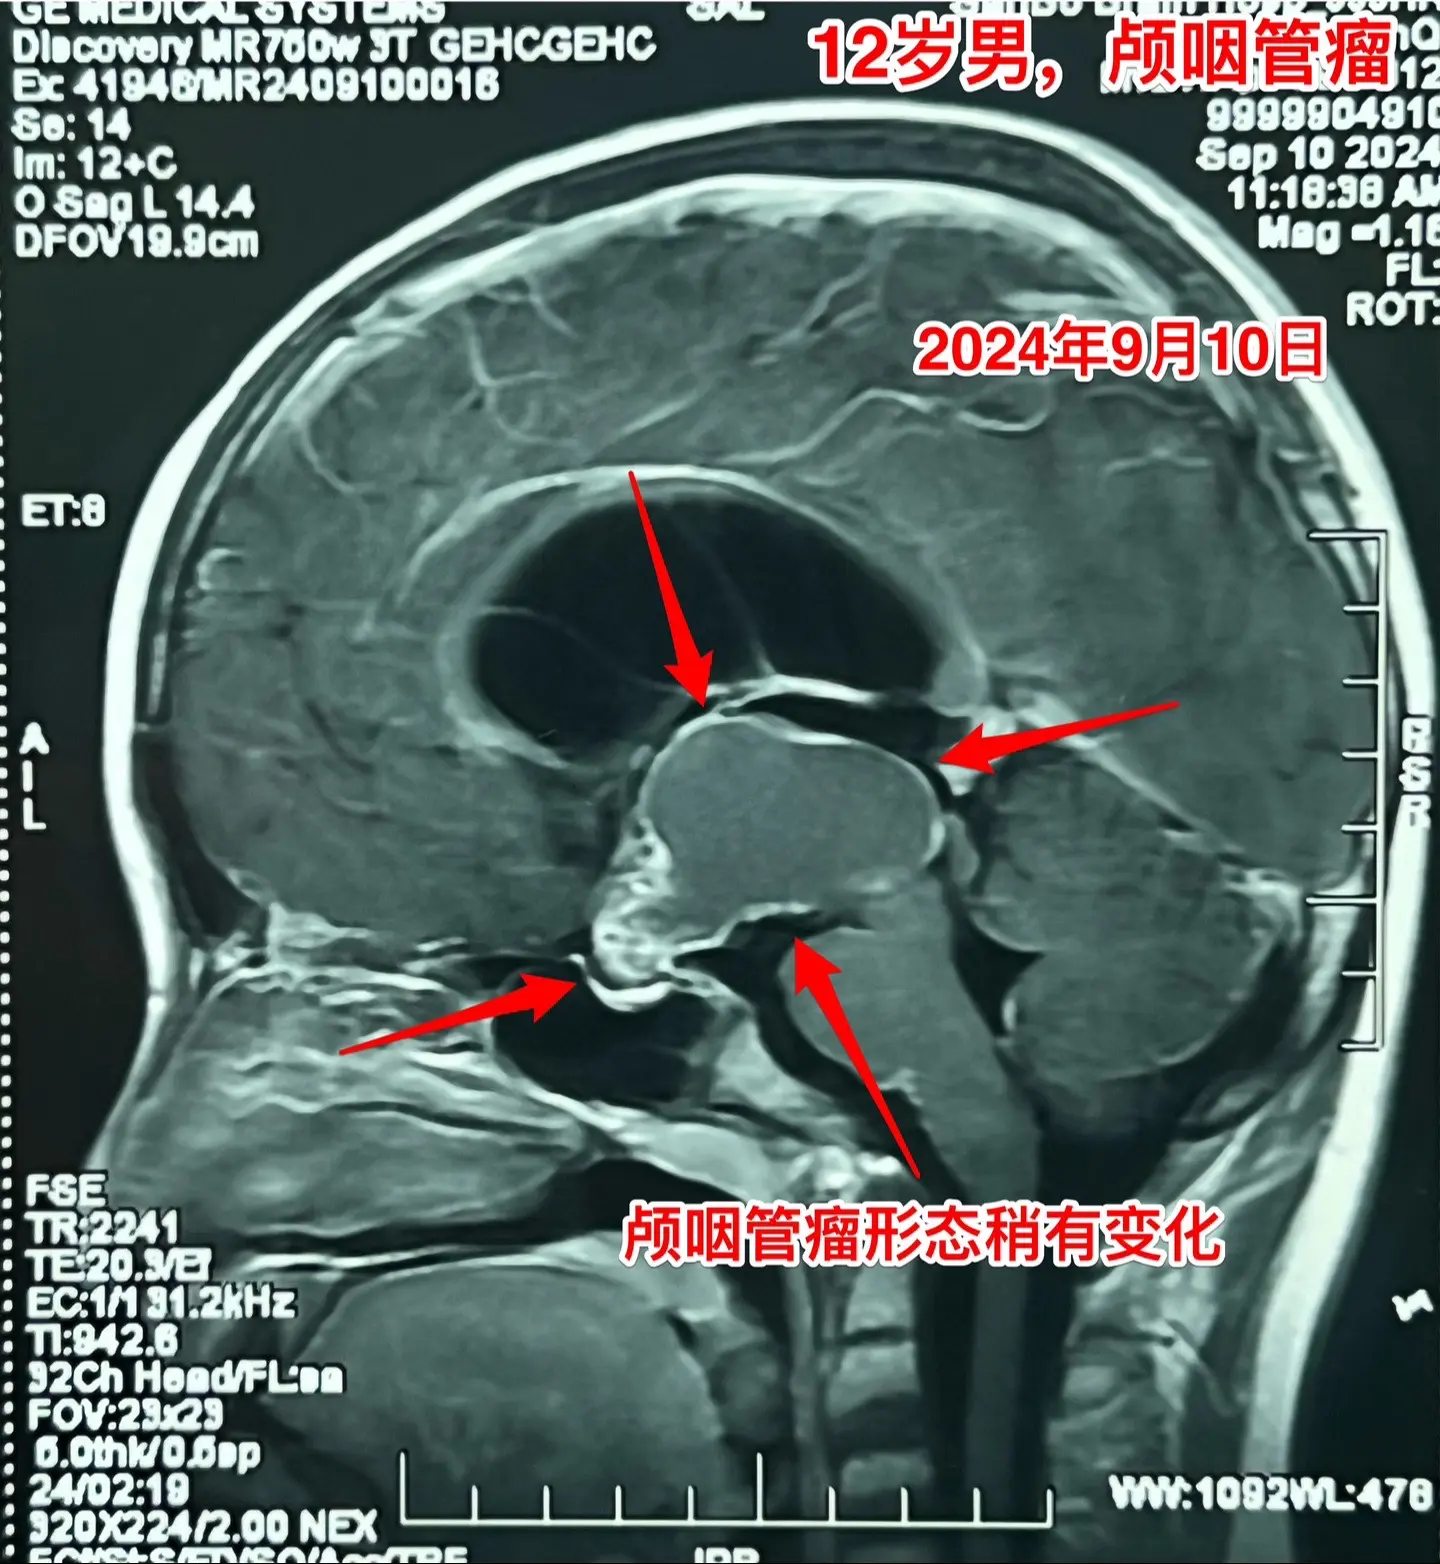

12岁南京男孩子头痛、呕吐。平时感觉身体很好,9月7日因头痛、呕吐到医院检查发现脑部长了颅咽管瘤,并且有脑积水。 9月9日到我院住院。住院时头痛、呕吐症状减轻了。复查磁共振显示颅咽管瘤的形态稍有变化,脑积水似乎有减轻。测视力发现他的视力有下降。这个颅咽管瘤生长的时间预计有两年时间,患儿症状不严重,最终因脑积水出现头痛、呕吐症状才发病。仔细检查还是可以发现一些蛛丝马迹,比如视力下降。颅咽管瘤有时会自动变小,很可能是肿瘤囊破裂了。囊变小了,脑积水就减轻了,头痛、呕吐症状就减轻了。 9月19日行开颅手术,将颅咽管瘤完全切除。手术后患者感觉视力有好转。希望肿瘤永不复发。